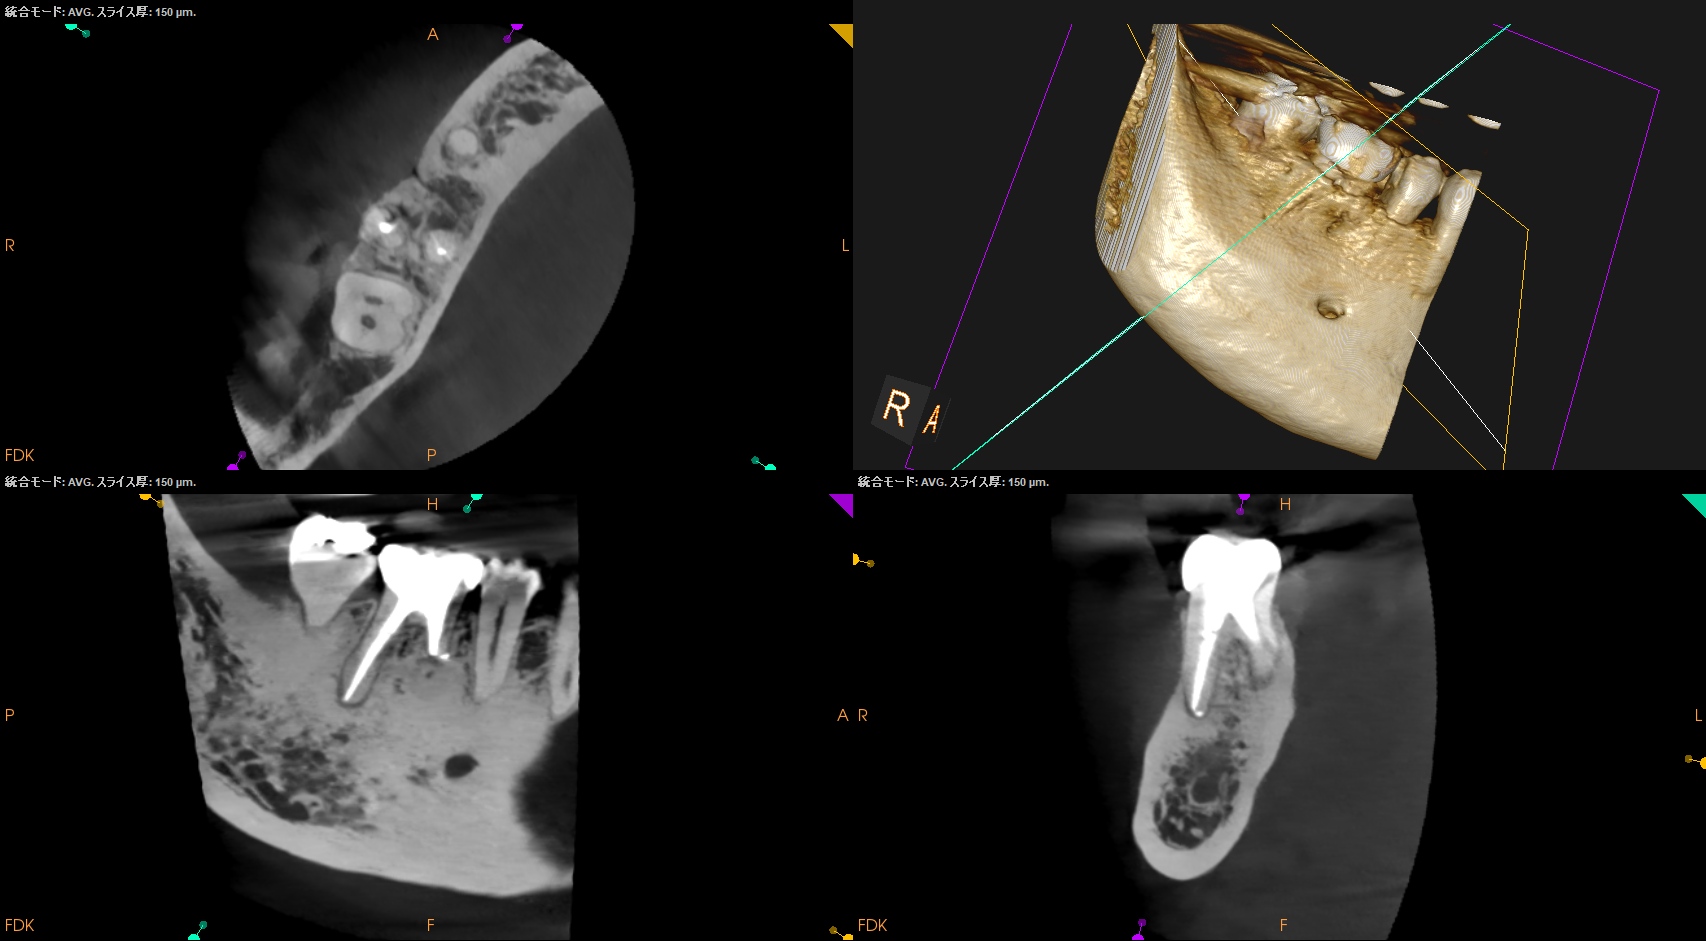

#30 M Apicoectomy, D+Radix Re-RCT 2yr recall(2025.10.17)

初診時、1年後と比較した。

トランスポーテーションしたMは劇的に治癒している。

Dも然りだ。

が、トランスポーテーションしているRadixはまだ治癒途中だろう。

が、患者さんに症状もないことからこの歯の状況はさらに2年後に経過を見せてもらうこととなった。

次回が、#30 M Apicoectomy, D+Radix Re-RCT 4yr recallとなる。